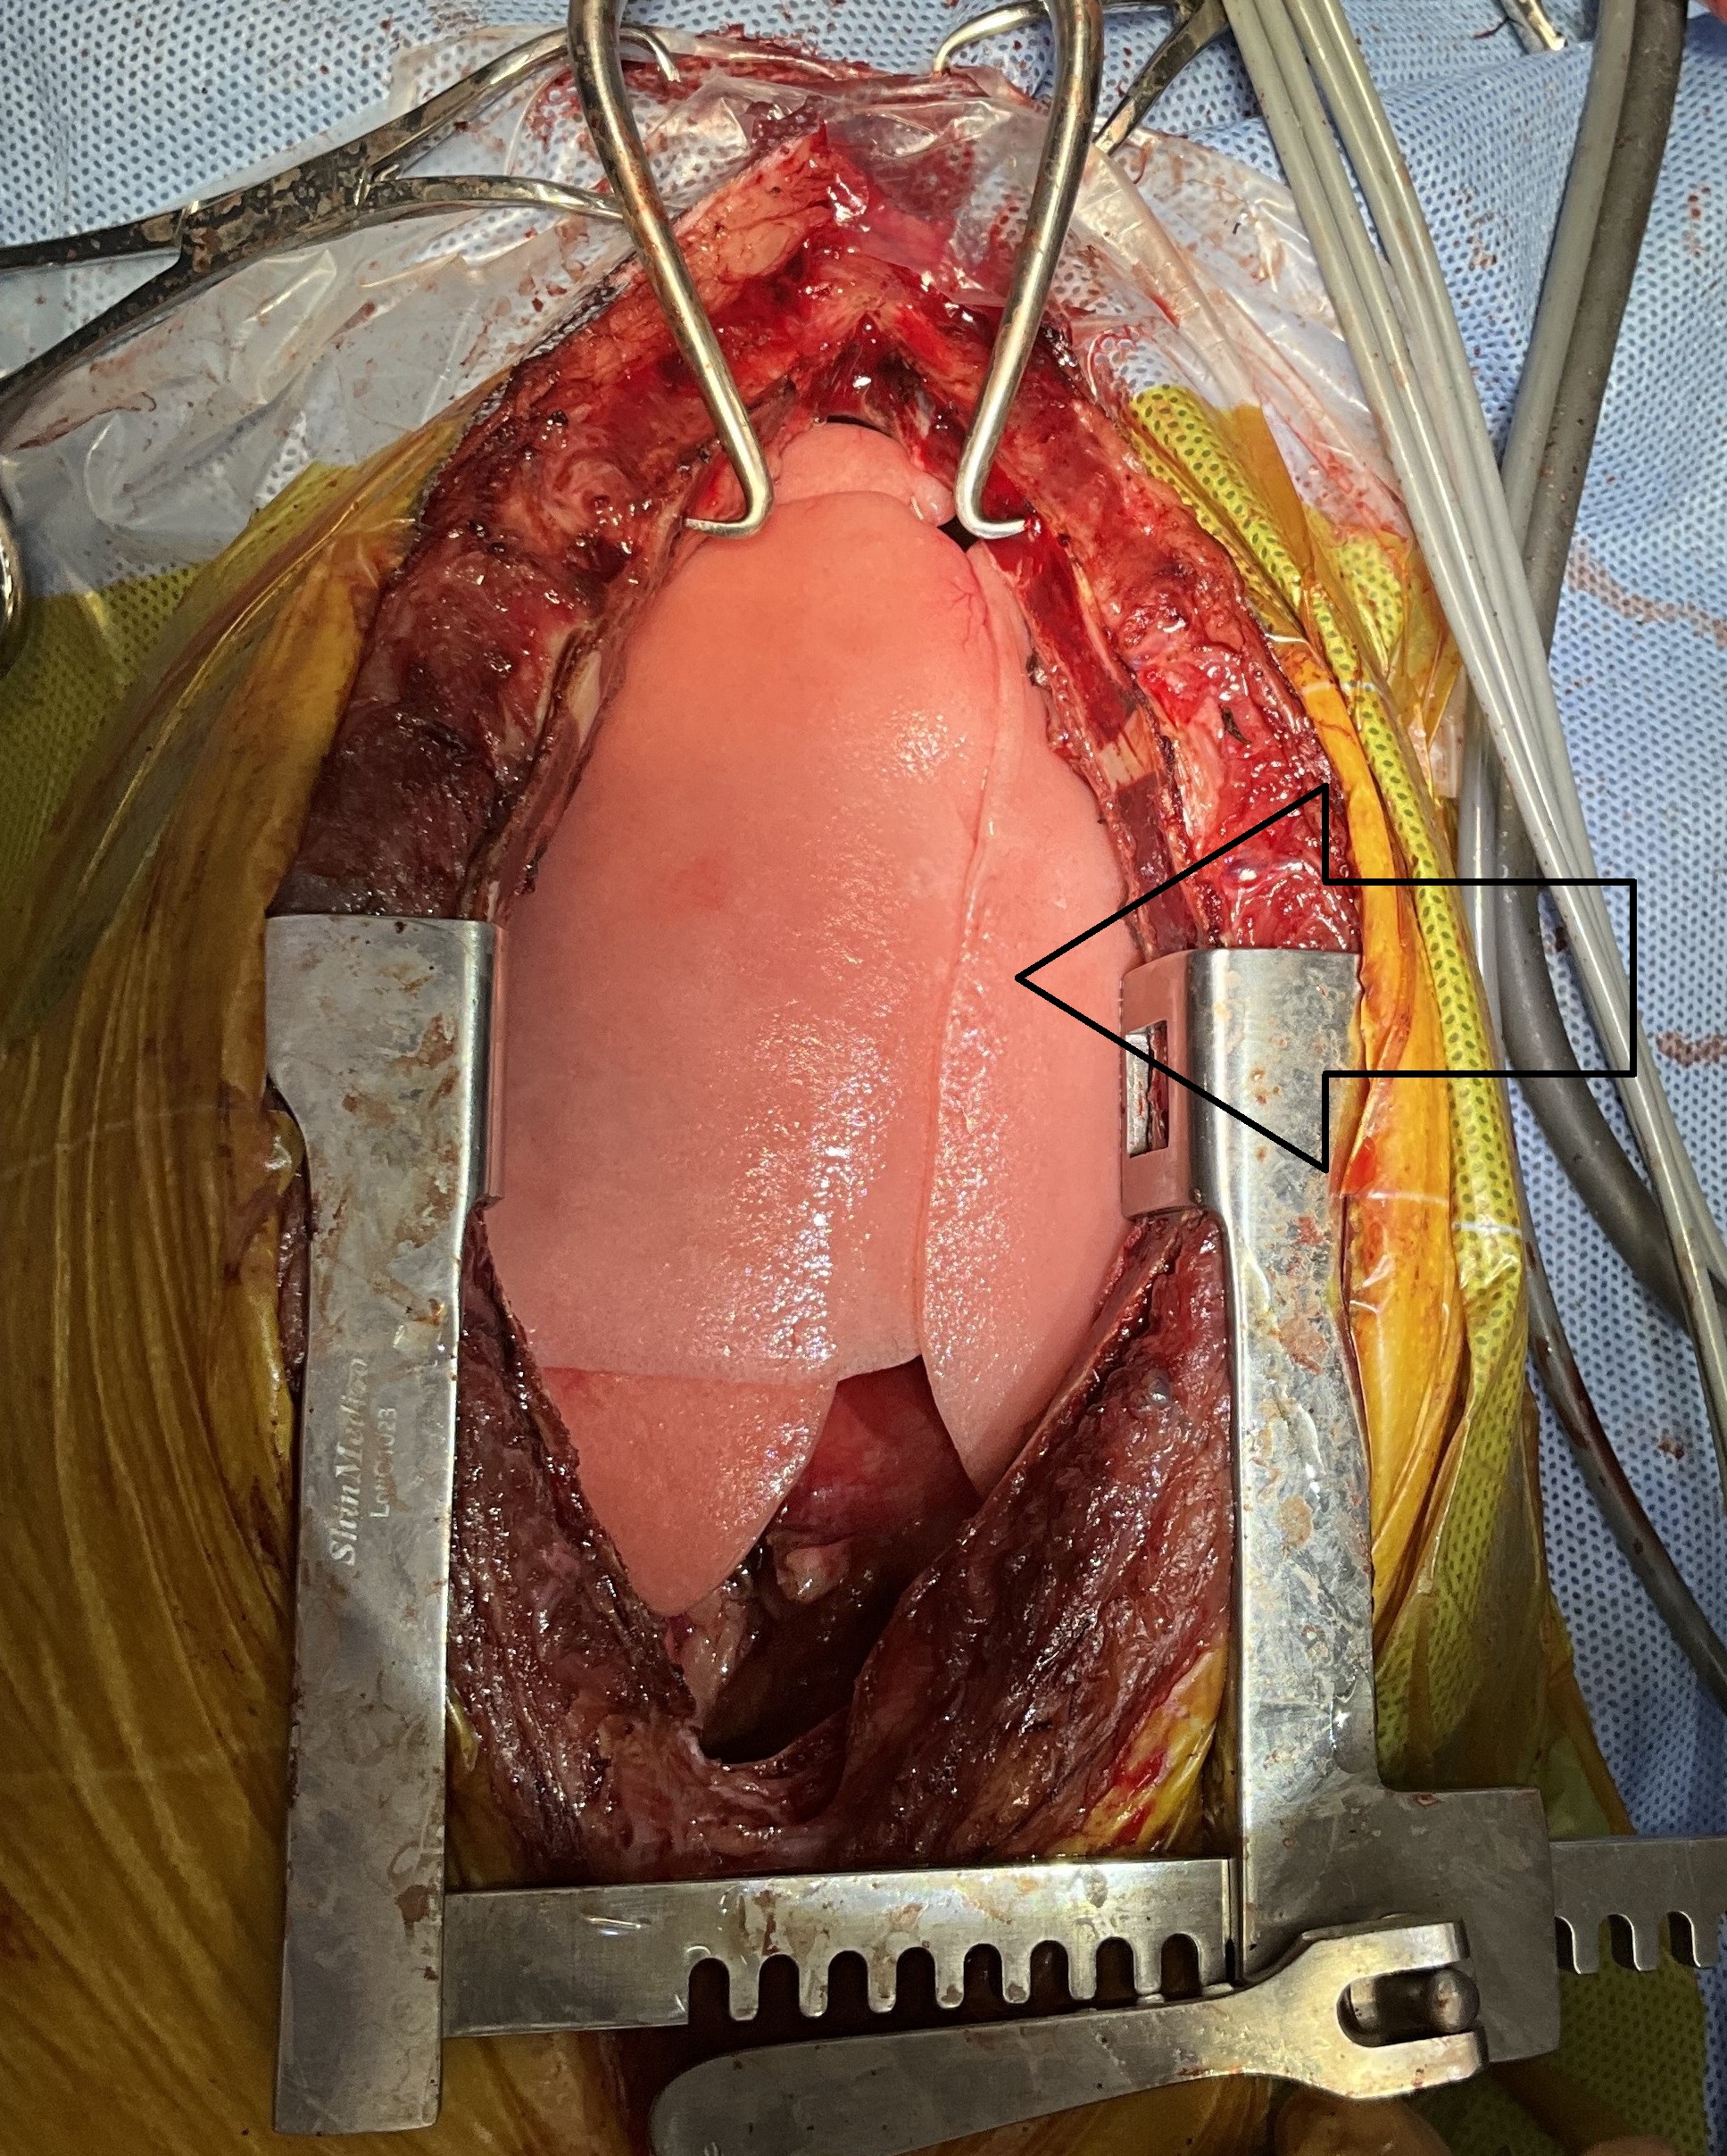

前胸部腫瘤摘出手術

胸骨を切開すると、前胸部に大きな腫瘤(白丸)が肉眼的に確認できました。

腫瘤(黄矢印)は心臓(黒矢印)にも癒着しており、心膜ごと切除する必要がありました。

また、前大静脈への癒着が認められたため、慎重に剥離操作を行いました。

腫瘤に流入する血管は一本一本丁寧に処理しました。